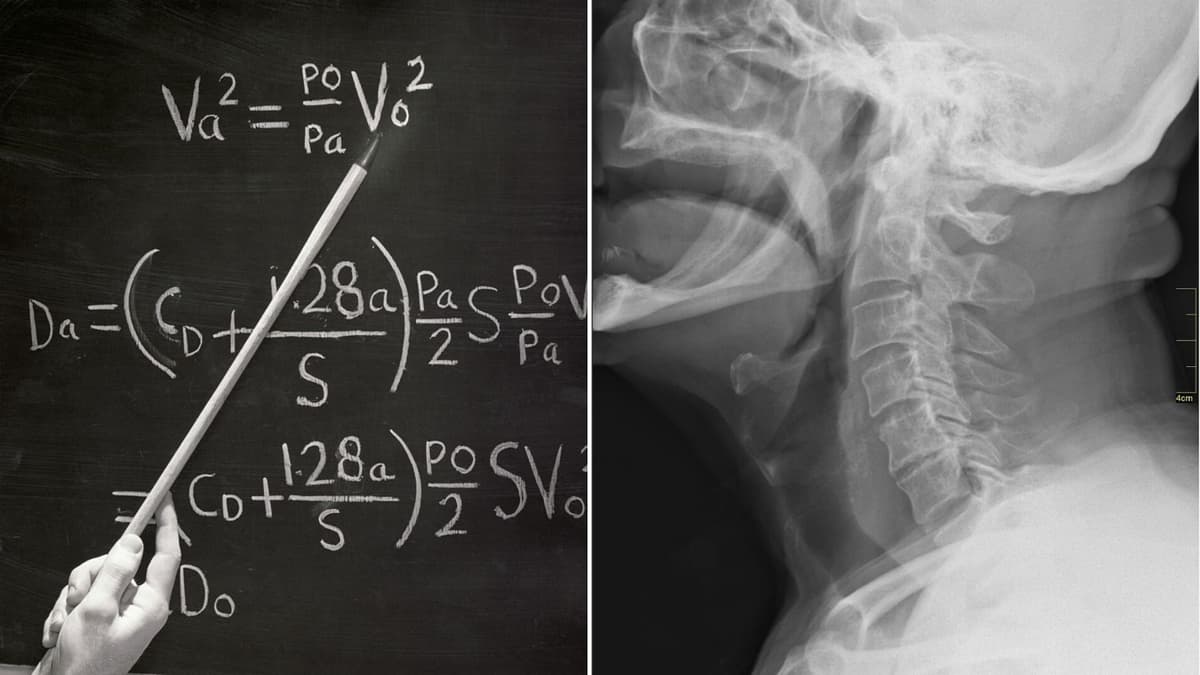

Model Matematika Baru Membantu Mengatasi Masalah Sulit Menelan dengan Akurat

Dalam proses menelan, esofagus bekerja seperti gelombang dengan otot yang mengencang dan mengendur secara terkoordinasi agar makanan dan minuman bisa turun ke lambung dengan lancar. Penelitian terbaru yang menggunakan alat canggih untuk mengukur tekanan di dalam esofagus mengungkap bahwa gerakan tersebut lebih kompleks dari pemahaman sebelumnya.

Para peneliti dari Kyushu University bekerjasama dengan Josai University dan Hokkaido University mengembangkan sebuah model matematika yang mampu mensimulasikan gerakan otot-otot tersebut secara detail, termasuk pengaturan saraf dan sinyal otak. Model ini juga menampilkan fungsi katup di bagian bawah esofagus yang terbuka dan tertutup pada waktu yang tepat.